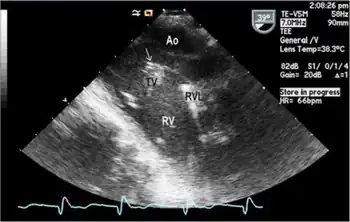

All of these organisms are part of the normal oropharyngeal flora, which grow slowly (up to 14 days), prefer a carbon dioxide–enriched atmosphere, and share an enhanced capacity to produce endocardial infections, especially in young children. Collectively, they account for 5–10% of cases of infective endocarditis involving native valves and are the most common Gram-negative cause of endocarditis among people who do not use drugs intravenously. They have been a frequent cause of culture-negative endocarditis. Culture-negative refers to an inability to produce a colony on regular agar plates because these bacteria are fastidious (require a specific nutrient).